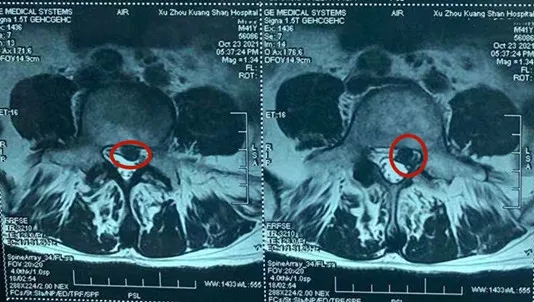

為了得到有效治療,王先生聽朋友介紹后慕名來到華潤(rùn)醫(yī)療徐州市礦山醫(yī)院求診,骨二科副主任顧署光接診后發(fā)現(xiàn),王先生的L4/L5椎間盤向椎管內(nèi)脫出,硬臘囊及神經(jīng)管受壓。

像王先生這樣的情況,就屬于典型的椎管內(nèi)脫垂,壓住了神經(jīng)導(dǎo)致他疼痛難忍。